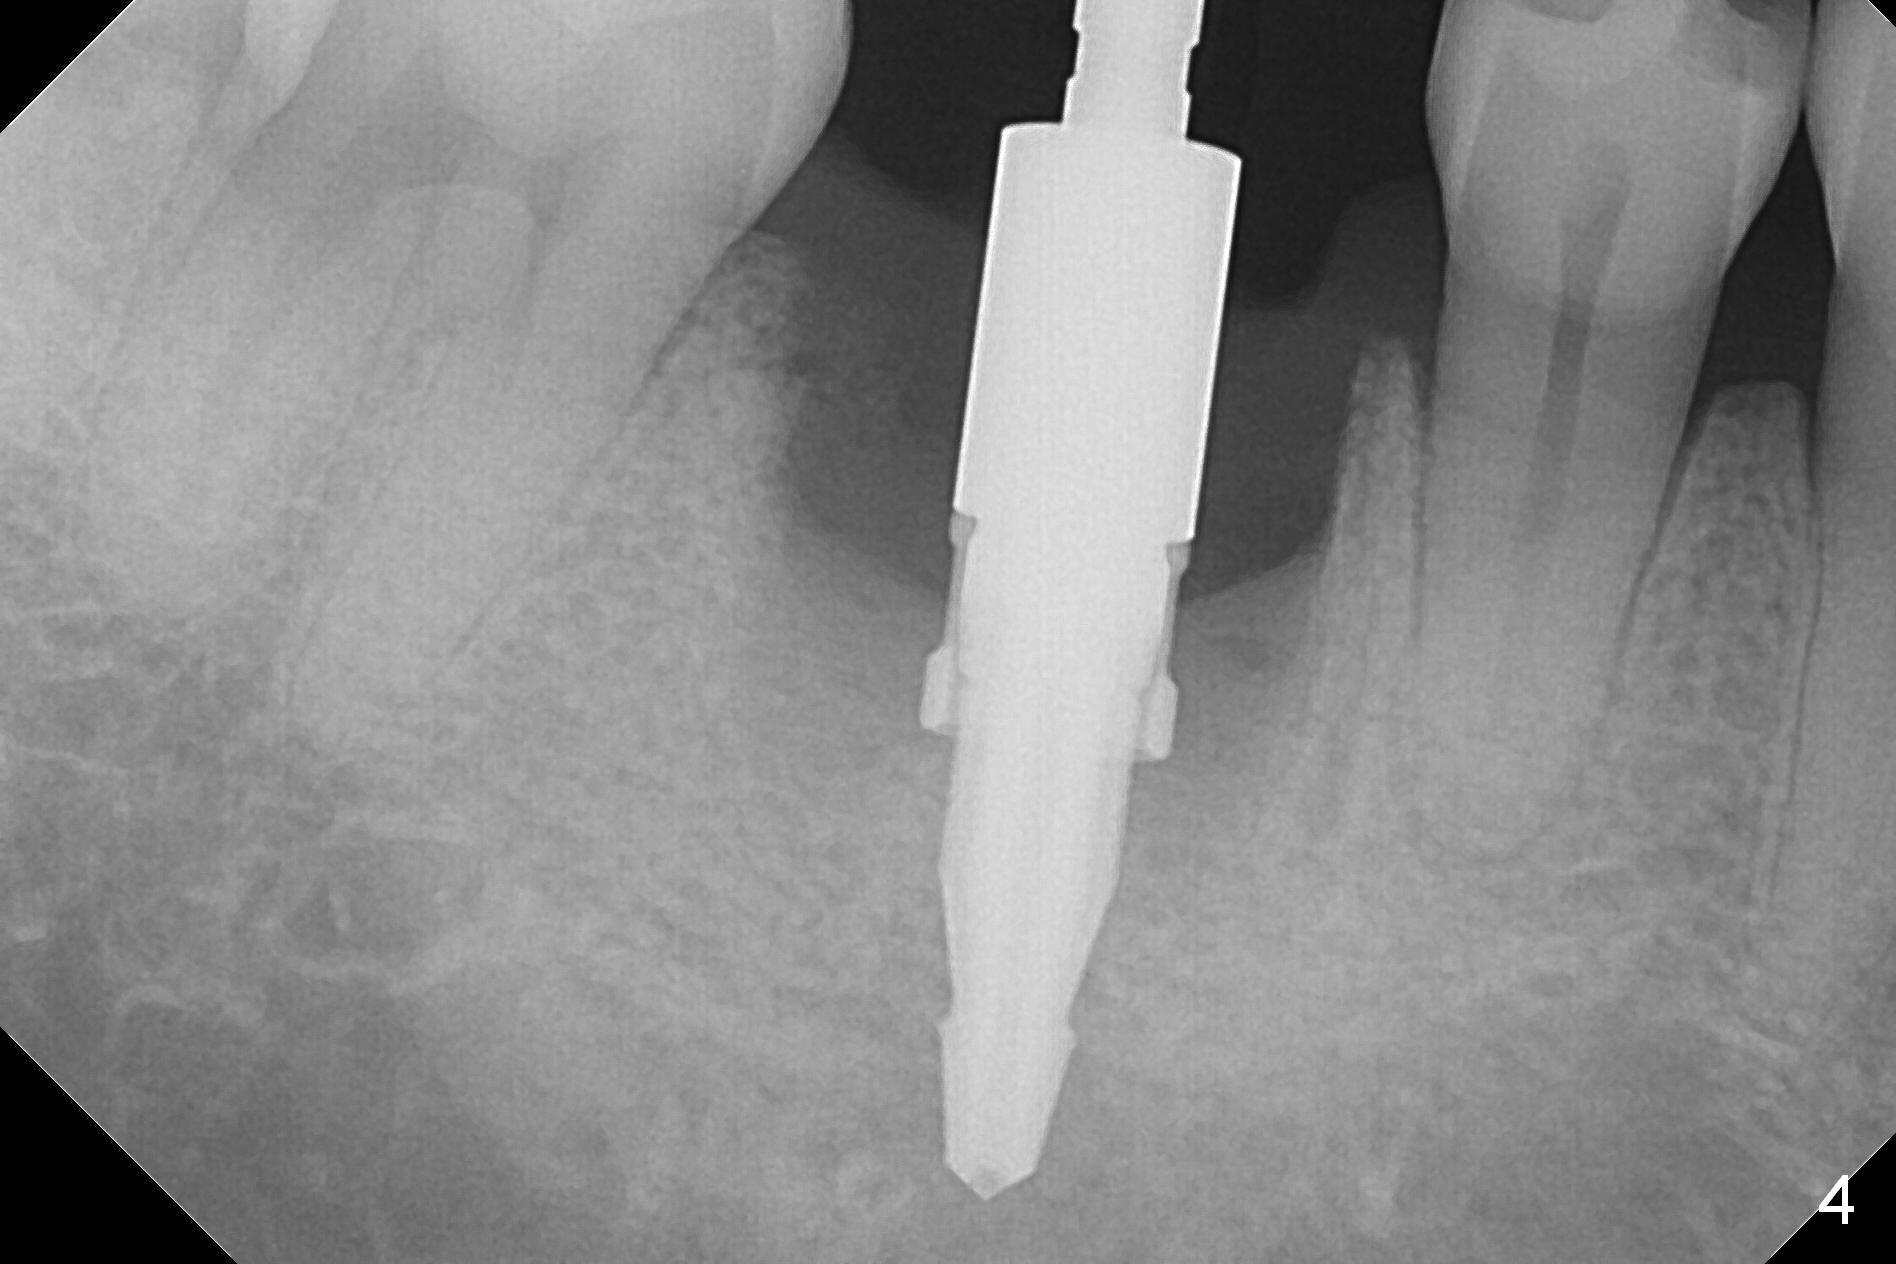

After extraction of the tooth #30 with Class V furcation involvement (Fig.1 (>),2 (L: lingual)), initial osteotomy depth is 8 mm with infiltration anesthesia, but a parallel pin is able to be inserted for 16 mm without pain (Fig.3). There is oozing from the osteotomy. Osteotomy increases in diameter with depth at 8 mm (Fig.4 (3.8 mm drill),5 (5.3 mm tap)). As the Inferior Alveolar Canal (IAC) is indistinct with increased pain during osteotomy, a 5.9x6 mm implant is placed with >50 Ncm following Septocaine infiltration (Fig.6). When bone graft (Fig.7 *) and 7.8x5.5(6) mm abutment (Fig.7,8) are placed, panoramic X-ray is taken (Fig.9). There appears to be a thick layer of spongy bone in the posterior mandible between the red and yellow dashed lines (Fig.5,9). Panoramic X-ray and/or CBCT should be taken if preop PA does not reveal IAC. This patient seems to be a bruxer. There are mandibular tori. Bone loss (furcation involvement) is not proportional to his oral hygiene status. Functional loading (progressive) should be delayed due to bruxism and the short implant.